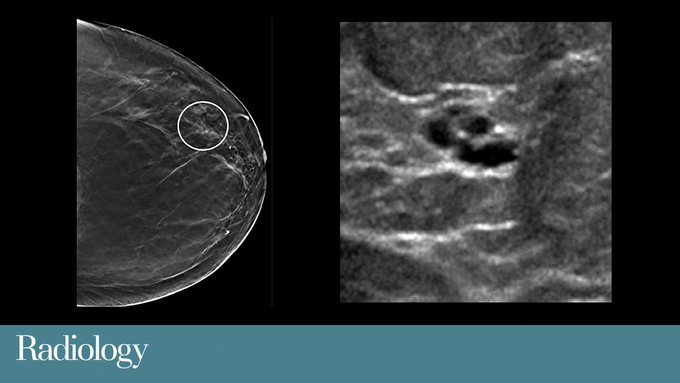

Tomosynthesis shows advantages over digital mammography including increased cancer detection and fewer false positive findings, according to a newly published five-year study in @radiology_rsna: http://bit.ly/3cPwurc #BreastImaging #mammo

Recently published research in @radiology_rsna further supports existing literature that breast lesions characterized as clustered microcysts demonstrate a very low risk of malignancy. http://bit.ly/39EVi2S #BreastImaging